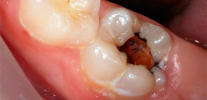

L'immagine seguente mostra schematicamente il classico sviluppo della pulpite - dopo carie profonde:

La causa più comune (eziologia) della pulpite è carie profonde. Nel processo di approfondimento della cavità cariata, si verifica la penetrazione diretta o indiretta dei microbi nel tessuto pulpare. Con accesso diretto, l'infezione va direttamente alla polpa aperta e con accesso indiretto, attraverso i tubuli dentinali che penetrano nello spessore della dentina.